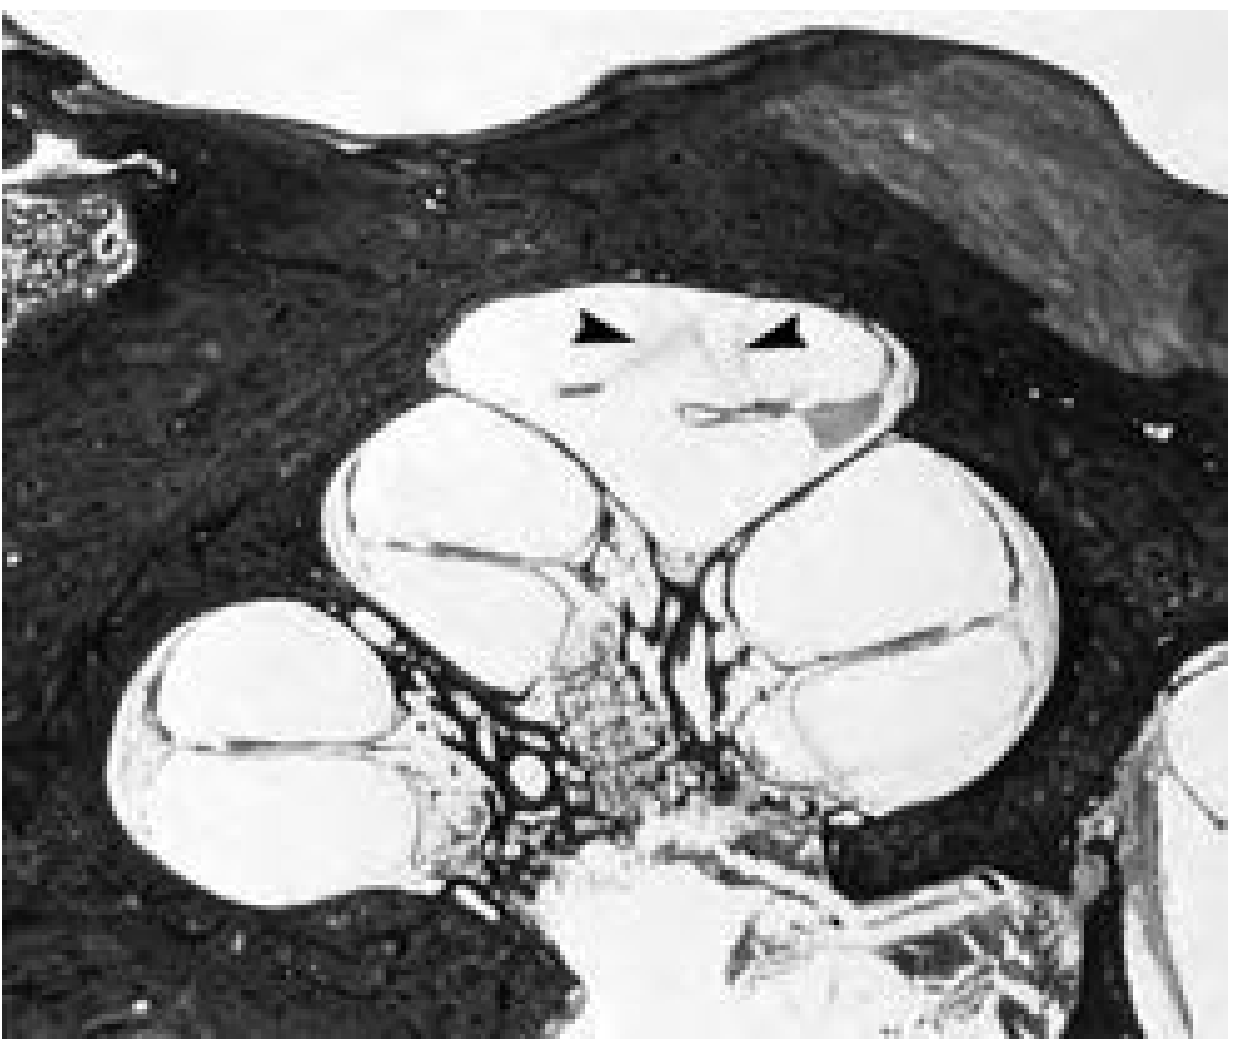

Photomicrograph of human cochlea cross-section showing endolymphatic hydrops — Reissner membrane distended into the scala tympani (arrowheads) — Cummings Otolaryngology